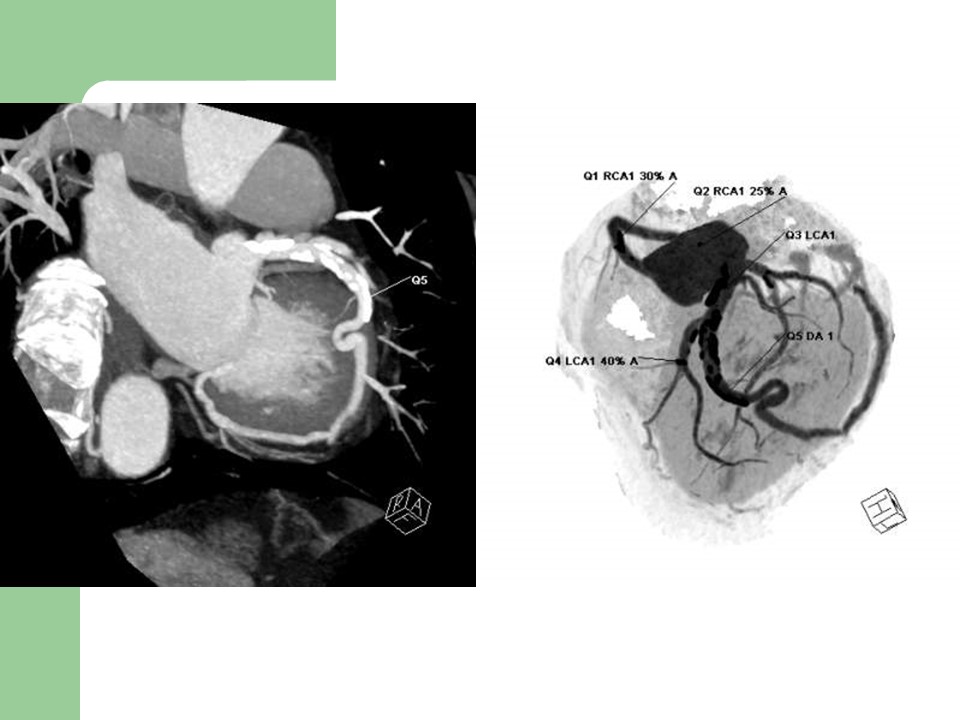

“冠状动脉常见疾病的双源CT表现” 的相关文章